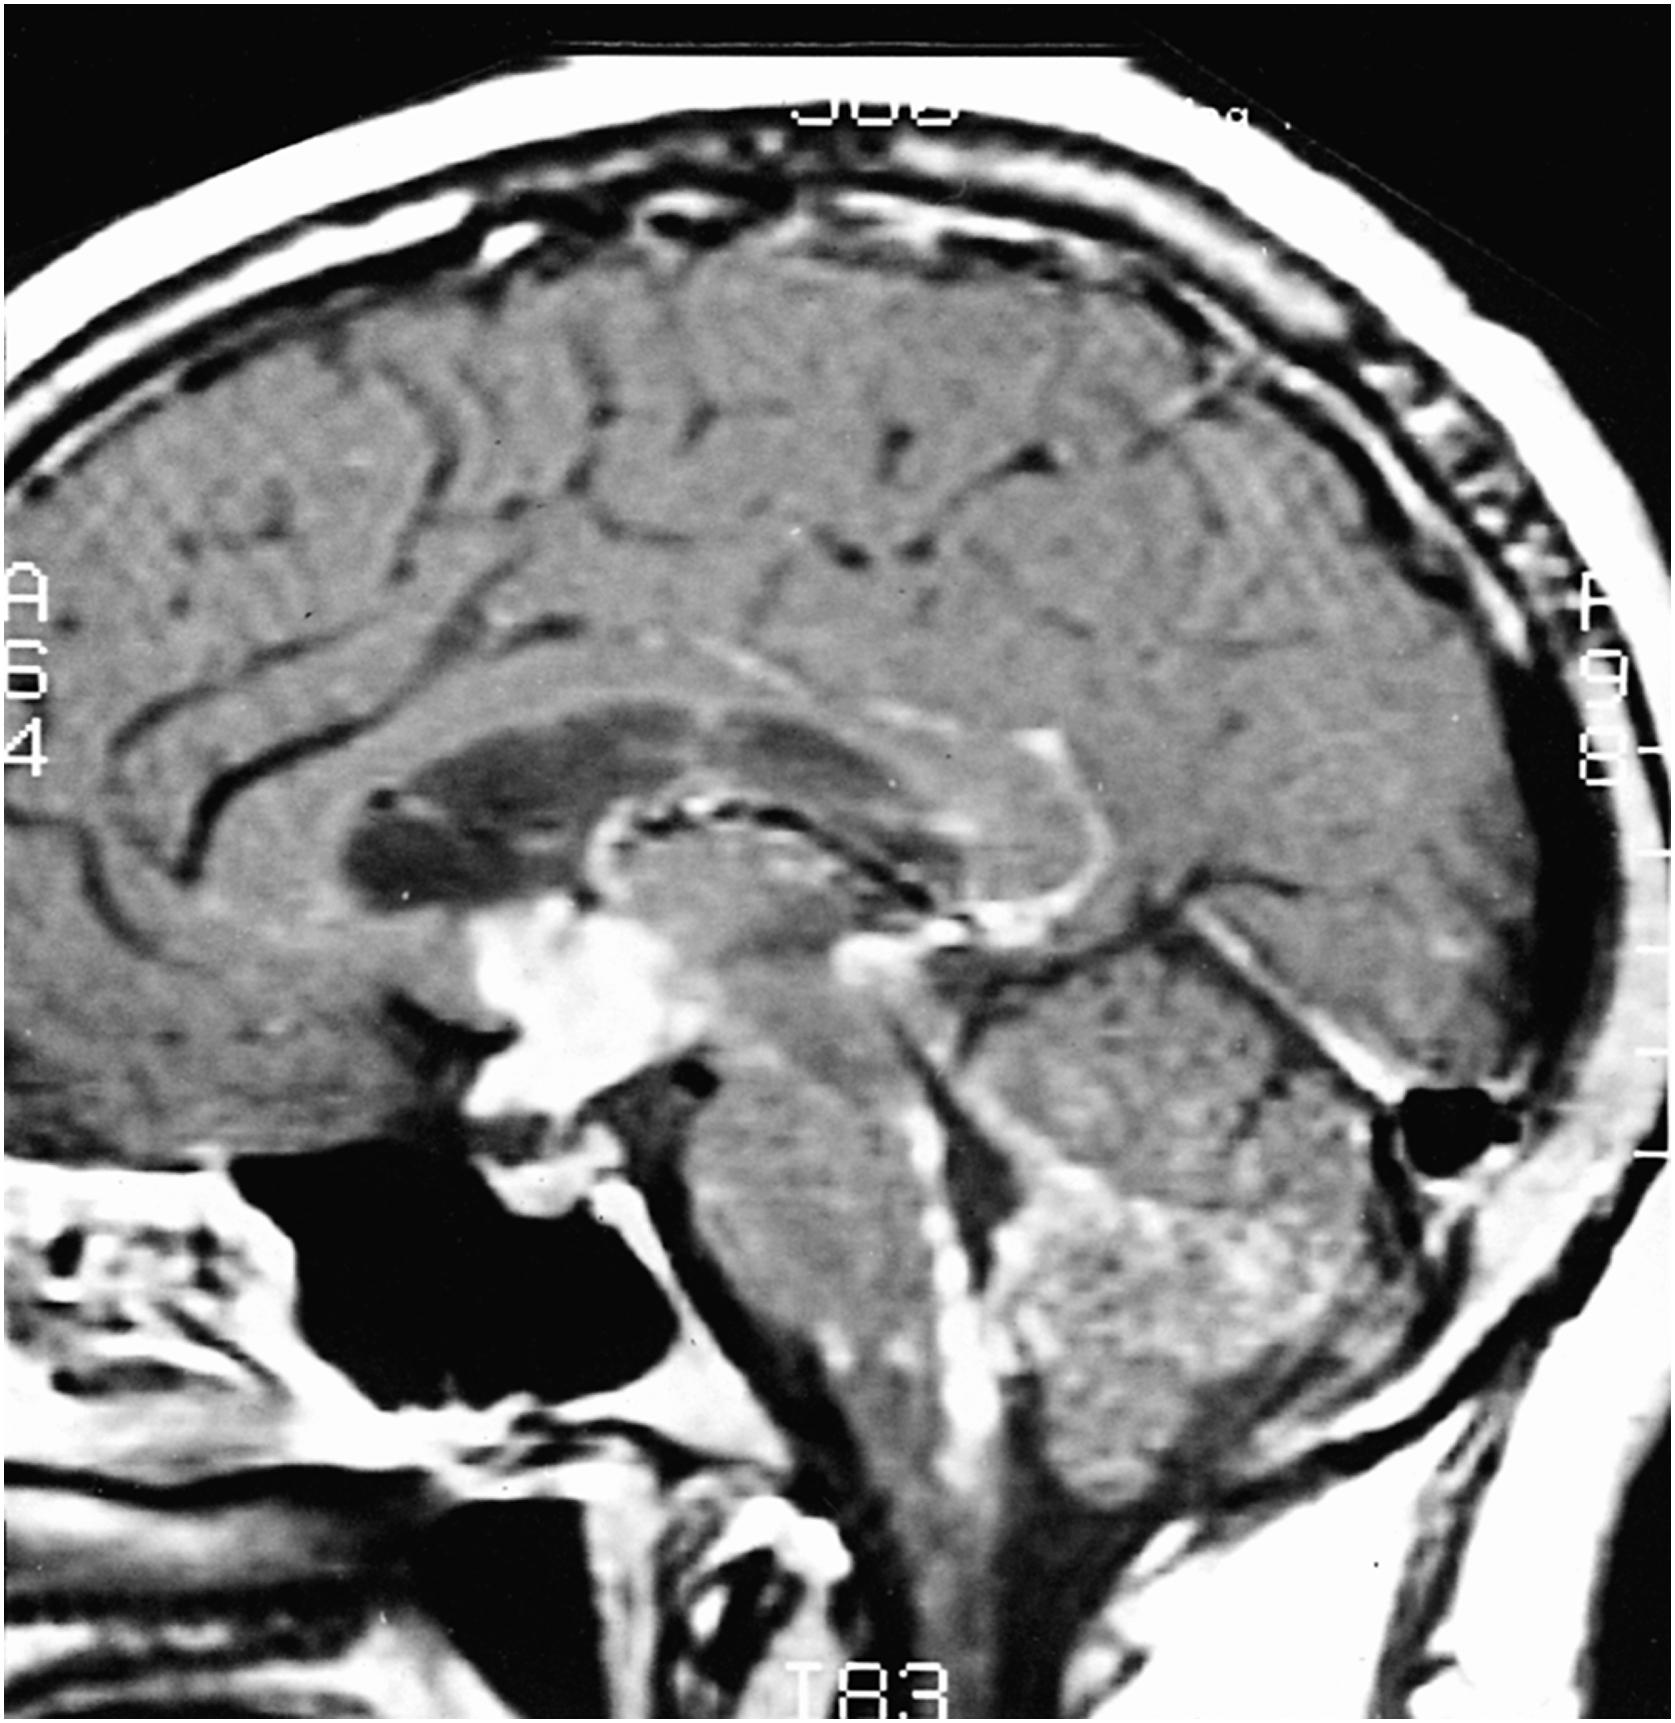

Any of the neuroendocrinologic systems can be affected by sarcoidosis due to either a hypothalamic or pituitary granulomatous mass or a more diffuse local inflammation. Given the predilection of sarcoidosis for the basal meninges ( Fig. 49-8 ), the relative frequency of such endocrinologic disturbances is not surprising. Anterior pituitary dysfunction is more common than posterior pituitary dysfunction. Potential endocrinologic manifestations include gonadotropin deficiency, TSH deficiency, hyperprolactinemia, and diabetes insipidus. Hypothalamic disorders vary in their effect on vegetative functions. A disorder of thirst is the most common hypothalamic disorder related to neurosarcoidosis and is attributed to a change in the hypothalamic osmostat. Less commonly, the syndrome of inappropriate secretion of antidiuretic hormone occurs. Neurosarcoidosis-induced disruptions of hypothalamic–pituitary function can also cause problems with appetite, libido, temperature control, weight regulation, and sleep. Because neuroendocrinologic involvement is relatively common in individuals with CNS sarcoidosis, patients with more than just an isolated facial palsy probably merit a thorough evaluation with specific attention to hypothyroidism, hypocortisolism, hypogonadism, and hyperprolactinemia. Furthermore, in affected patients, contrast-enhanced MRI may identify inflammation of the hypothalamic–pituitary structures or surrounding meninges. Unfortunately, hormonal abnormalities may persist even after effective control of neurosarcoidosis inflammation.

Figure 49-8, Cranial MRI, sagittal section, T1-weighted image with gadolinium, showing hypothalamic and pituitary involvement by sarcoidosis.